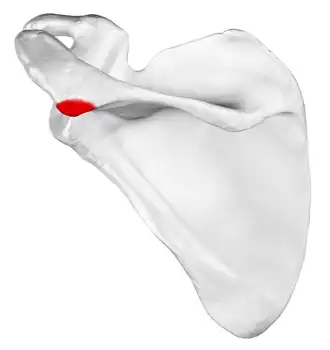

Left scapula, posterior view. Acromion shown in red.